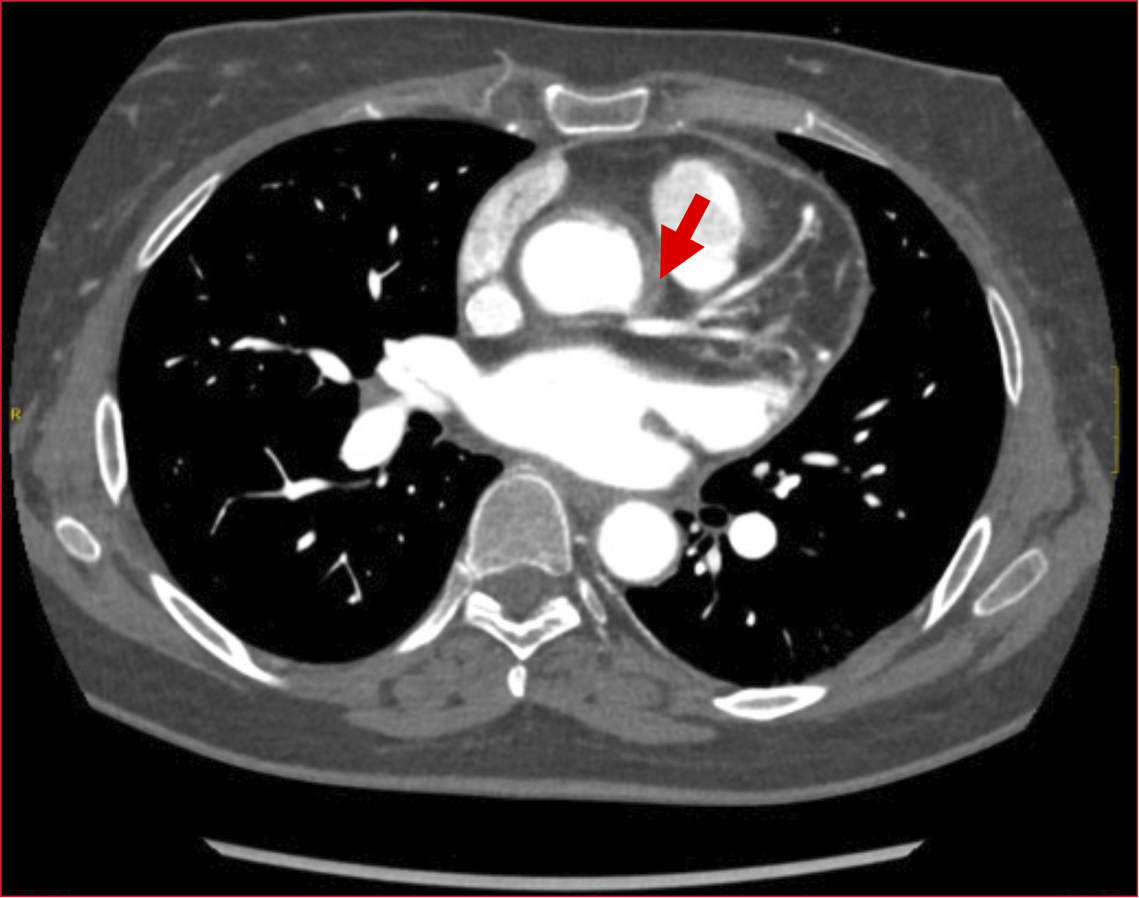

Return to Article Details High-risk non-ST-elevation acute coronary syndrome as a severe clinical manifestation of Cogan's Syndrome